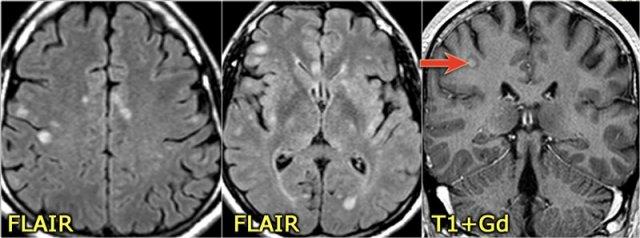

Ở một bệnh nhân khác có các tổn thương không đặc hiệu trong tủy sống.

Chỉ dựa vào khảo sát cột sống đơn thuần, chúng ta có một chẩn đoán phân biệt rộng.

Tuy nhiên khi khảo sát thêm não, sẽ rõ ràng rằng chúng ta đang đối mặt với MS.

Tiếp tục xem các hình ảnh của não.

Trong trường hợp này, các hình ảnh trên não rất hữu ích.

Vị trí của các tổn thương rất điển hình: cầu não, quanh não thất và dưới vỏ não.